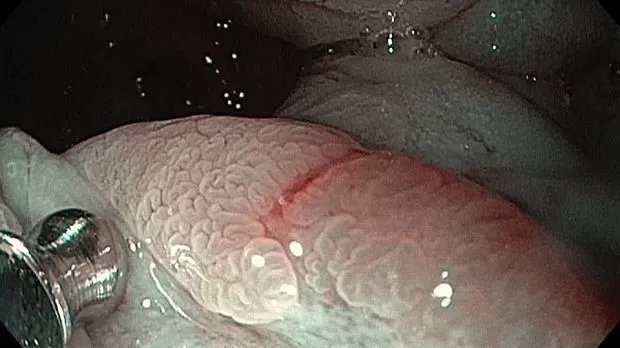

Публикации из социальных сетей: “Cobblestone esophagitis” (эзофагит со слизистой булыжной мостовой)

“Cobblestone esophagitis” (эзофагит со слизистой булыжной мостовой) - редкая эндоскопическая находка и ассоциируется с эозинофильным эзофагитом, кандидозом и пищеводом Барретта у взрослых. Он также может быть найден при тяжелом рефлюкс-эзофагите, вторичен к дистальной обструкции гастроинтестинального тракта. В нашем случае - это пациент после с 9-летним стажем бандажирования кардиального отдела желудка, признаками дуоденостаза, фундальной эрозивной гастропатией, расширением пищевода и уровнем жидкости в нем при горизонтальном положении, грыжи ПОД, эрозивно-язвенном дистальном эзофагите.. Пациент просто пришел удалить полип в прямой кишке и заодно посмотреть, что творится в желудке.... Ацетообеление+NBI+биопсия. ИПП на 3-4 мес и повтор для решения о Барретте.